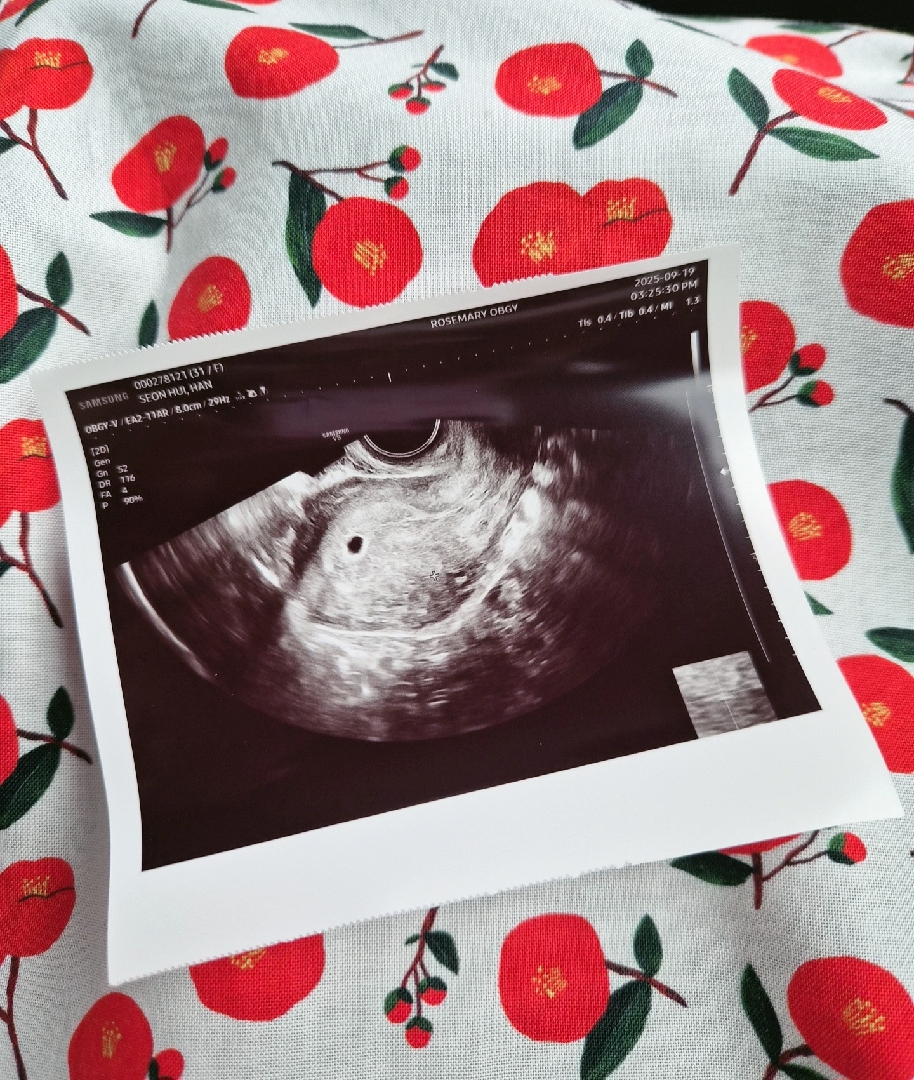

아기집 보고왔어요❣️❣️

배란 22일차!! 0.48이래요ㅎㅎ 배란16일차에 피검수치 128로 살짝 낮지않나 했는데 아기집이라도 보고와서 기분이 좋아요💕 찔끔찔끔 소량의 출혈이 2주간 지속되고있는데 원장쌤이 별말없으시더라구요... 별문제없어서 그런거겠죵..?ㅎㅎ 난황보는 날이 기다려져요!!